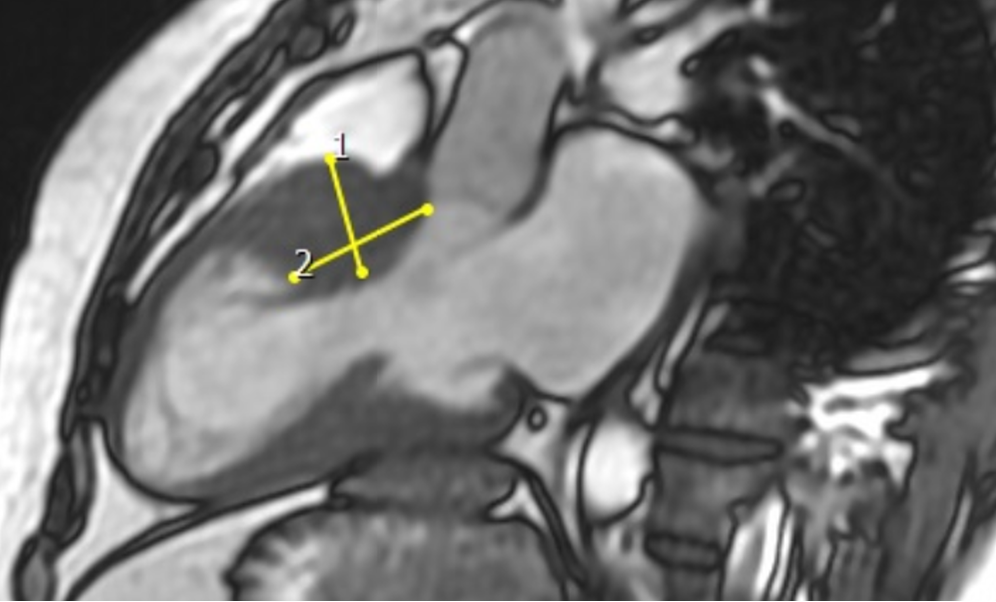

Planificarea intervenției chirurgicale presupune cunoașterea cu exactitate a anatomiei locale, fiecare caz de CMH fiind practic unic din punct de vedere al dispunerii hipertrofiei și al modificărilor valvulare mitrale. Acestea sunt studiate prin imagistică multimodală- folosind ecocardiografia clasică transtoracică, ecografia transesofagiană, |CT cardiac si mai ales rezonanța magnetică cardiacă.Elementele urmărite sunt lungimea cu care valva anterioară depășește pe cea posterioară, deplasarea punctului de coaptare al valvei mitrale spre anterior in tractul de ejecție al VS, rotația mușchilor papilari cu deplasarea cuspei anterioare către anterior, fixarea comisurii anterioare prin benzi musculare, aderențele dintre mușchii papilari și pereții liberi ai VS care împiedică funcționarea corectă în sistolă și tracțiunea pânzei valvulare înspre septul interventricular, prezența cordajelor secundare și a discontinuității mitro-aortice.

Figura 2. Masurarea grosimii mușchiului cardiac în zona care determină obstrucția în vederea miectomiei (eliminării mușchiului în exces). Măsurătorile sunt făcute pe imaginile de rezonanță magnetică, care oferă o rezoluție excelentă, evitându-se astfel pericolul unei secționări în exces, care ar duce la perforarea mușchiului.